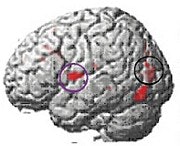

At the beginning of the study, MRI scans of the 20 dyslexic subjects contrasted sharply with those of the 12 normal readers in the control group; the dyslexic subjects' scans showed a lack of activity in the language-critical temporal regions of the brain.

Brain function in child with no reading disability (top); brain function in child with developmental dyslexia (middle); children with dyslexia show increased brain function after training (below). Images courtesy of Elise Temple, Ph.D.

At the end of the eighth week, the investigators found that, among the dyslectic subjects, areas of the brain critical to reading skills had become activated, and had begun to function more normally. Other regions of the brain also showed activity on the MRI scans, suggesting a gradual compensatory process that would help the dyslexic subjects learn to read more fluently.